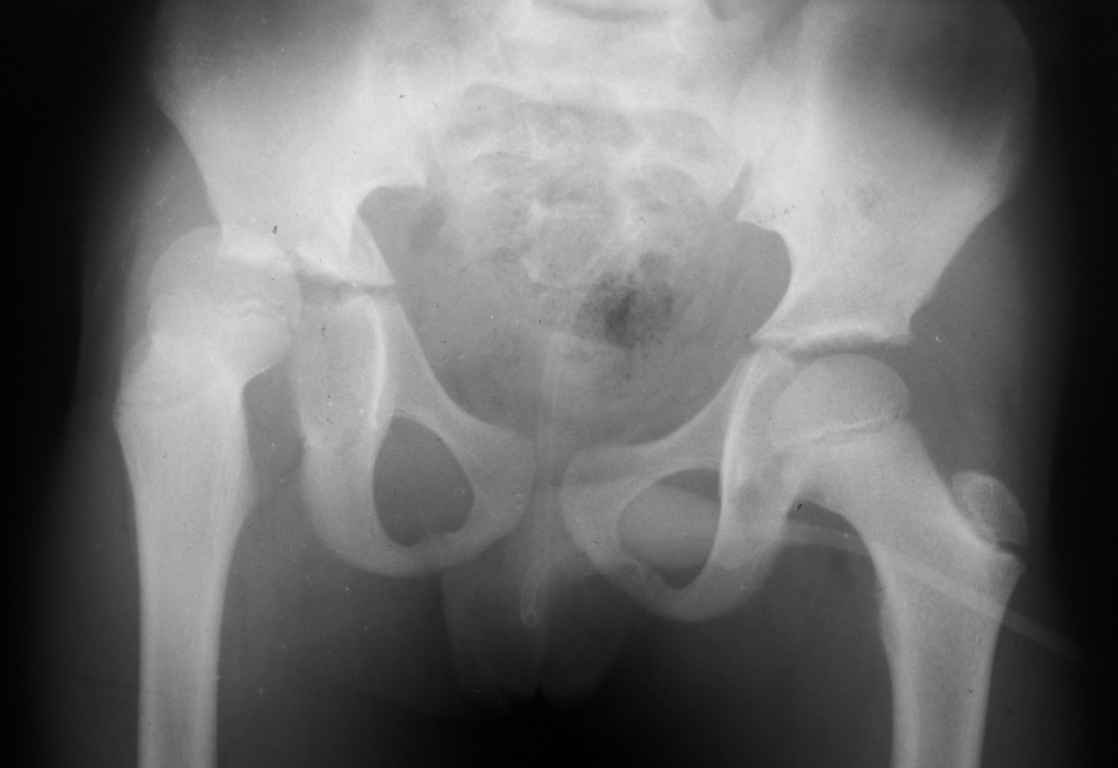

Перелом вертлужной впадины

Уважаемые коллеги, помогите определиться с тактикой лечения.Ребёнок 7 лет, травма 11.09.08, поступил с травматическим вывихом бедренной кости.

Вывих вправлен, конечность фиксирована на скелетном вытяжении. Что делать с переломом подвздошной кости? Лечить консерватино или оперировать?